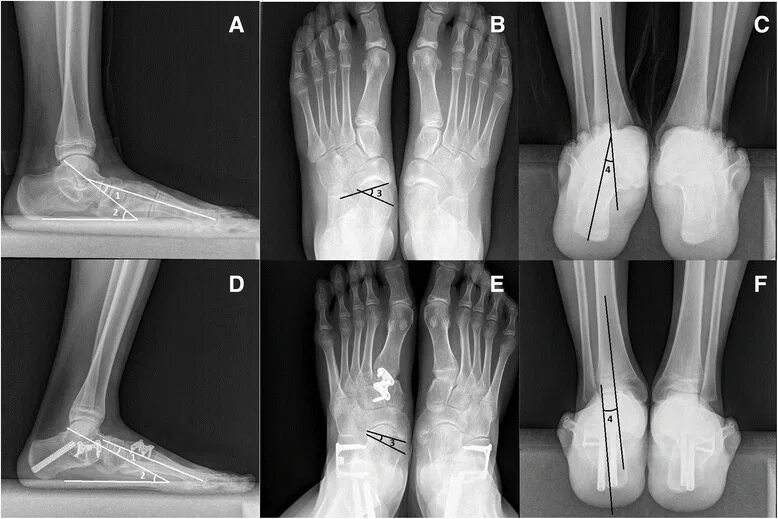

Пяточная остеотомия